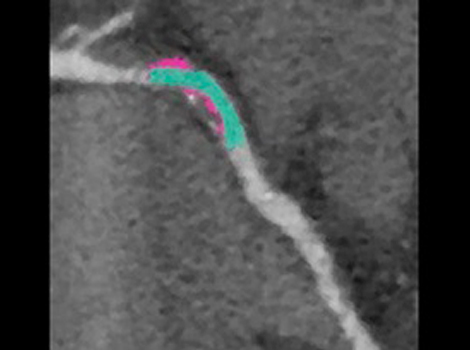

If considering catheter ablation as a treatment option, pre-procedure planning can involve use of MR or CT imaging to identify anatomical targets for the procedure and understand the extent of AF. These images can help guide decisions on necessity of left atrial appendage closure in certain populations.3

Revolution CT & CardioGraphe4

Achieve one-beat, whole heart acquisition for imaging or comprehensive cardiac assessment with or without beta blockers at any heart rate.5